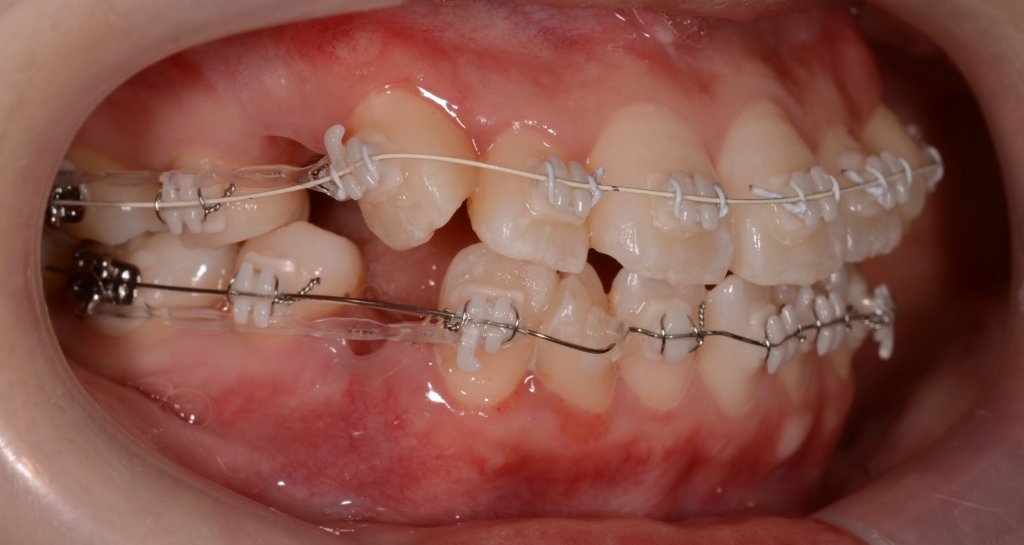

【治療装置】

マルチブラケットシステム(ハーフホワイトtype)で矯正を開始。

上下とも前歯を奥へ出来るだけたくさん引っ込めるよう治療を進めます。

その後、更なる点数アップを目指して仕上げの微調整を続けました。

左側に出っ歯の噛み合わせが残っていたので、左側のみ顎間ゴムを半年間頑張ってもらいました。

ついでに、歯並びの比較です

上段が矯正治療前、下段が矯正治療後